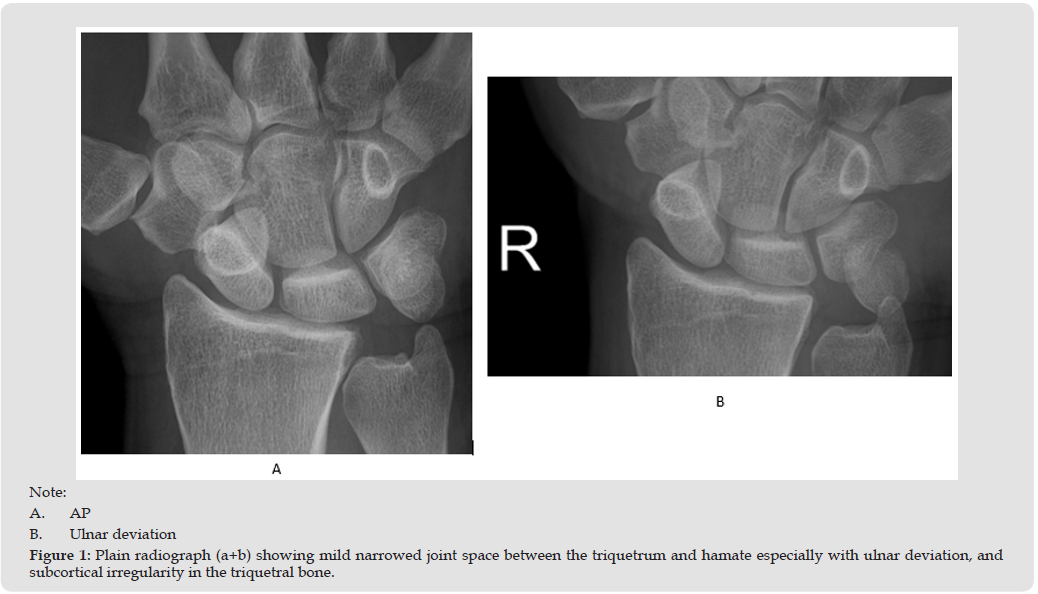

A 47-year-old right-hand dominant male social worker presented with persistent pain localized to the ulnar aspect of the wrist, without any preceding trauma. Initial evaluation by physical examination inspection revealed no swelling or deformity of the wrist. There was tenderness localized over the fovea region. Pain was elicited during passive dorsiflexion and ulnar deviation; no tenderness or prominence was noted over the ulnar head. The piano key sign was negative. The press test and synergy test were also negative. The range of motion was full with no limitation or pain, grip hand did not provoke any pain. Standard wrist radiographs (Figure 1) showed mild narrowed joint space between the triquetrum and hamate especially with ulnar deviation, and subcortical irregularity in the triquetral bone, but no fractures or dislocations. MRI imaging (Figure 2) demonstrated synovitis with post GD enhancement in the Triquetro-Hamate space due to Triquetro-Hamate impaction. Collaborative assessment by a hand orthopedic specialist and a musculoskeletal radiologist led to a conclusive diagnosis of Triquetrohamate Impaction Syndrome. The orthopedic surgeon did a corticosteroid injection in the Triquetro- hamate space with good results.

Triquetrohamate impingement syndrome is an uncommon but clinically significant etiology of ulnar-sided wrist pain. Differential diagnoses include TFCC tears, lunotriquetral instability, and ulnar impaction syndrome. The underlying pathology involves repetitive contact and degeneration between the triquetrum and hamate, leading to joint space narrowing, sclerosis, and osteophyte development. Radiological evaluation is essential, with CT and MRI offering detailed visualization of bone morphology and soft tissue changes. Plain radiographs4 may miss subtle changes, but radiographs with ulnar deviation may show narrowing of joint space, osteophytes and bone irregularities. Management typically begins conservatively, using NSAIDs, immobilization, and physiotherapy. In cases refractory to non-invasive measures, corticosteroid injections and surgical options such as arthroscopic debridement or partial resection may be considered. Surgical intervention generally yields favorable outcomes and improves functional restoration.